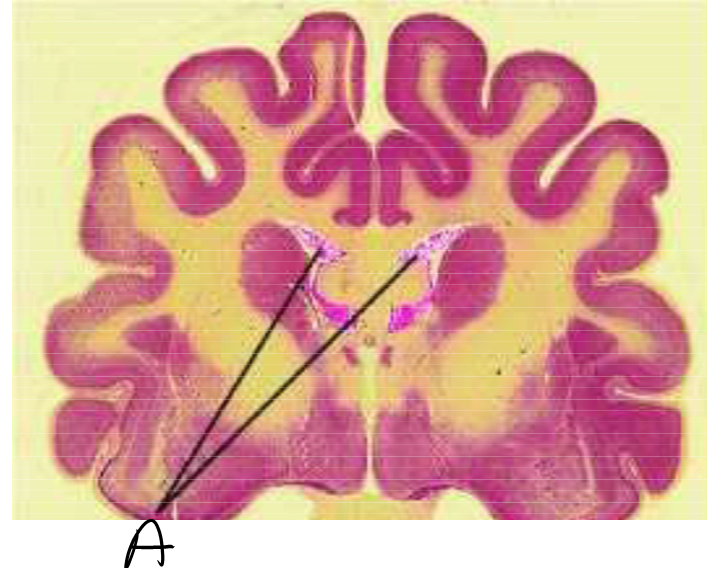

Q

What is the structure labed A?

A

Choriod Plexus